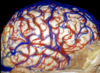

Central sulcus

Frontal lobe

Inferior frontal gyrus

Middle frontal gyrus

Occipital lobe

Parietal lobe

Parieto-occipital sulcus

Pre-occipital notch

Supramarginal gyrus

Sylvian fissure

Temporal lobe

Central lobe

Central sulcus

Frontal lobe

Inferior frontal gyrus

Inferior frontal sulcus

Middle frontal gyrus

Middle temporal gyrus

Occipital lobe

Parietal lobe

Post central gyrus

Postcentral sulcus

Precentral gyrus

Precentral sulcus

Premotor cortex

Subcentral gyrus

Superior frontal gyrus

Supramarginal gyrus

Vein of Trolard